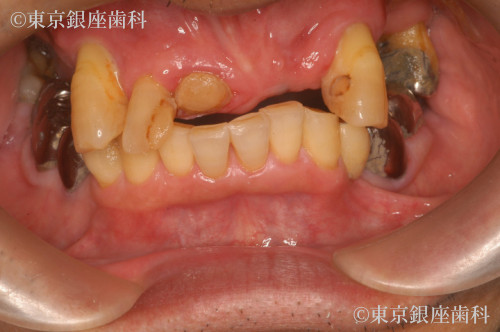

複数回の再埋入を経て骨と結合しづらい体質を克服した70歳代男性のインプラント症例

Before

骨と結合しづらい体質でインプラントが抜けることが続いたが、材料変更(HAコーティング等)で改善。2年半かけ安定した状態に。

上顎ワンデイインプラント+骨造成+サイナスリフト